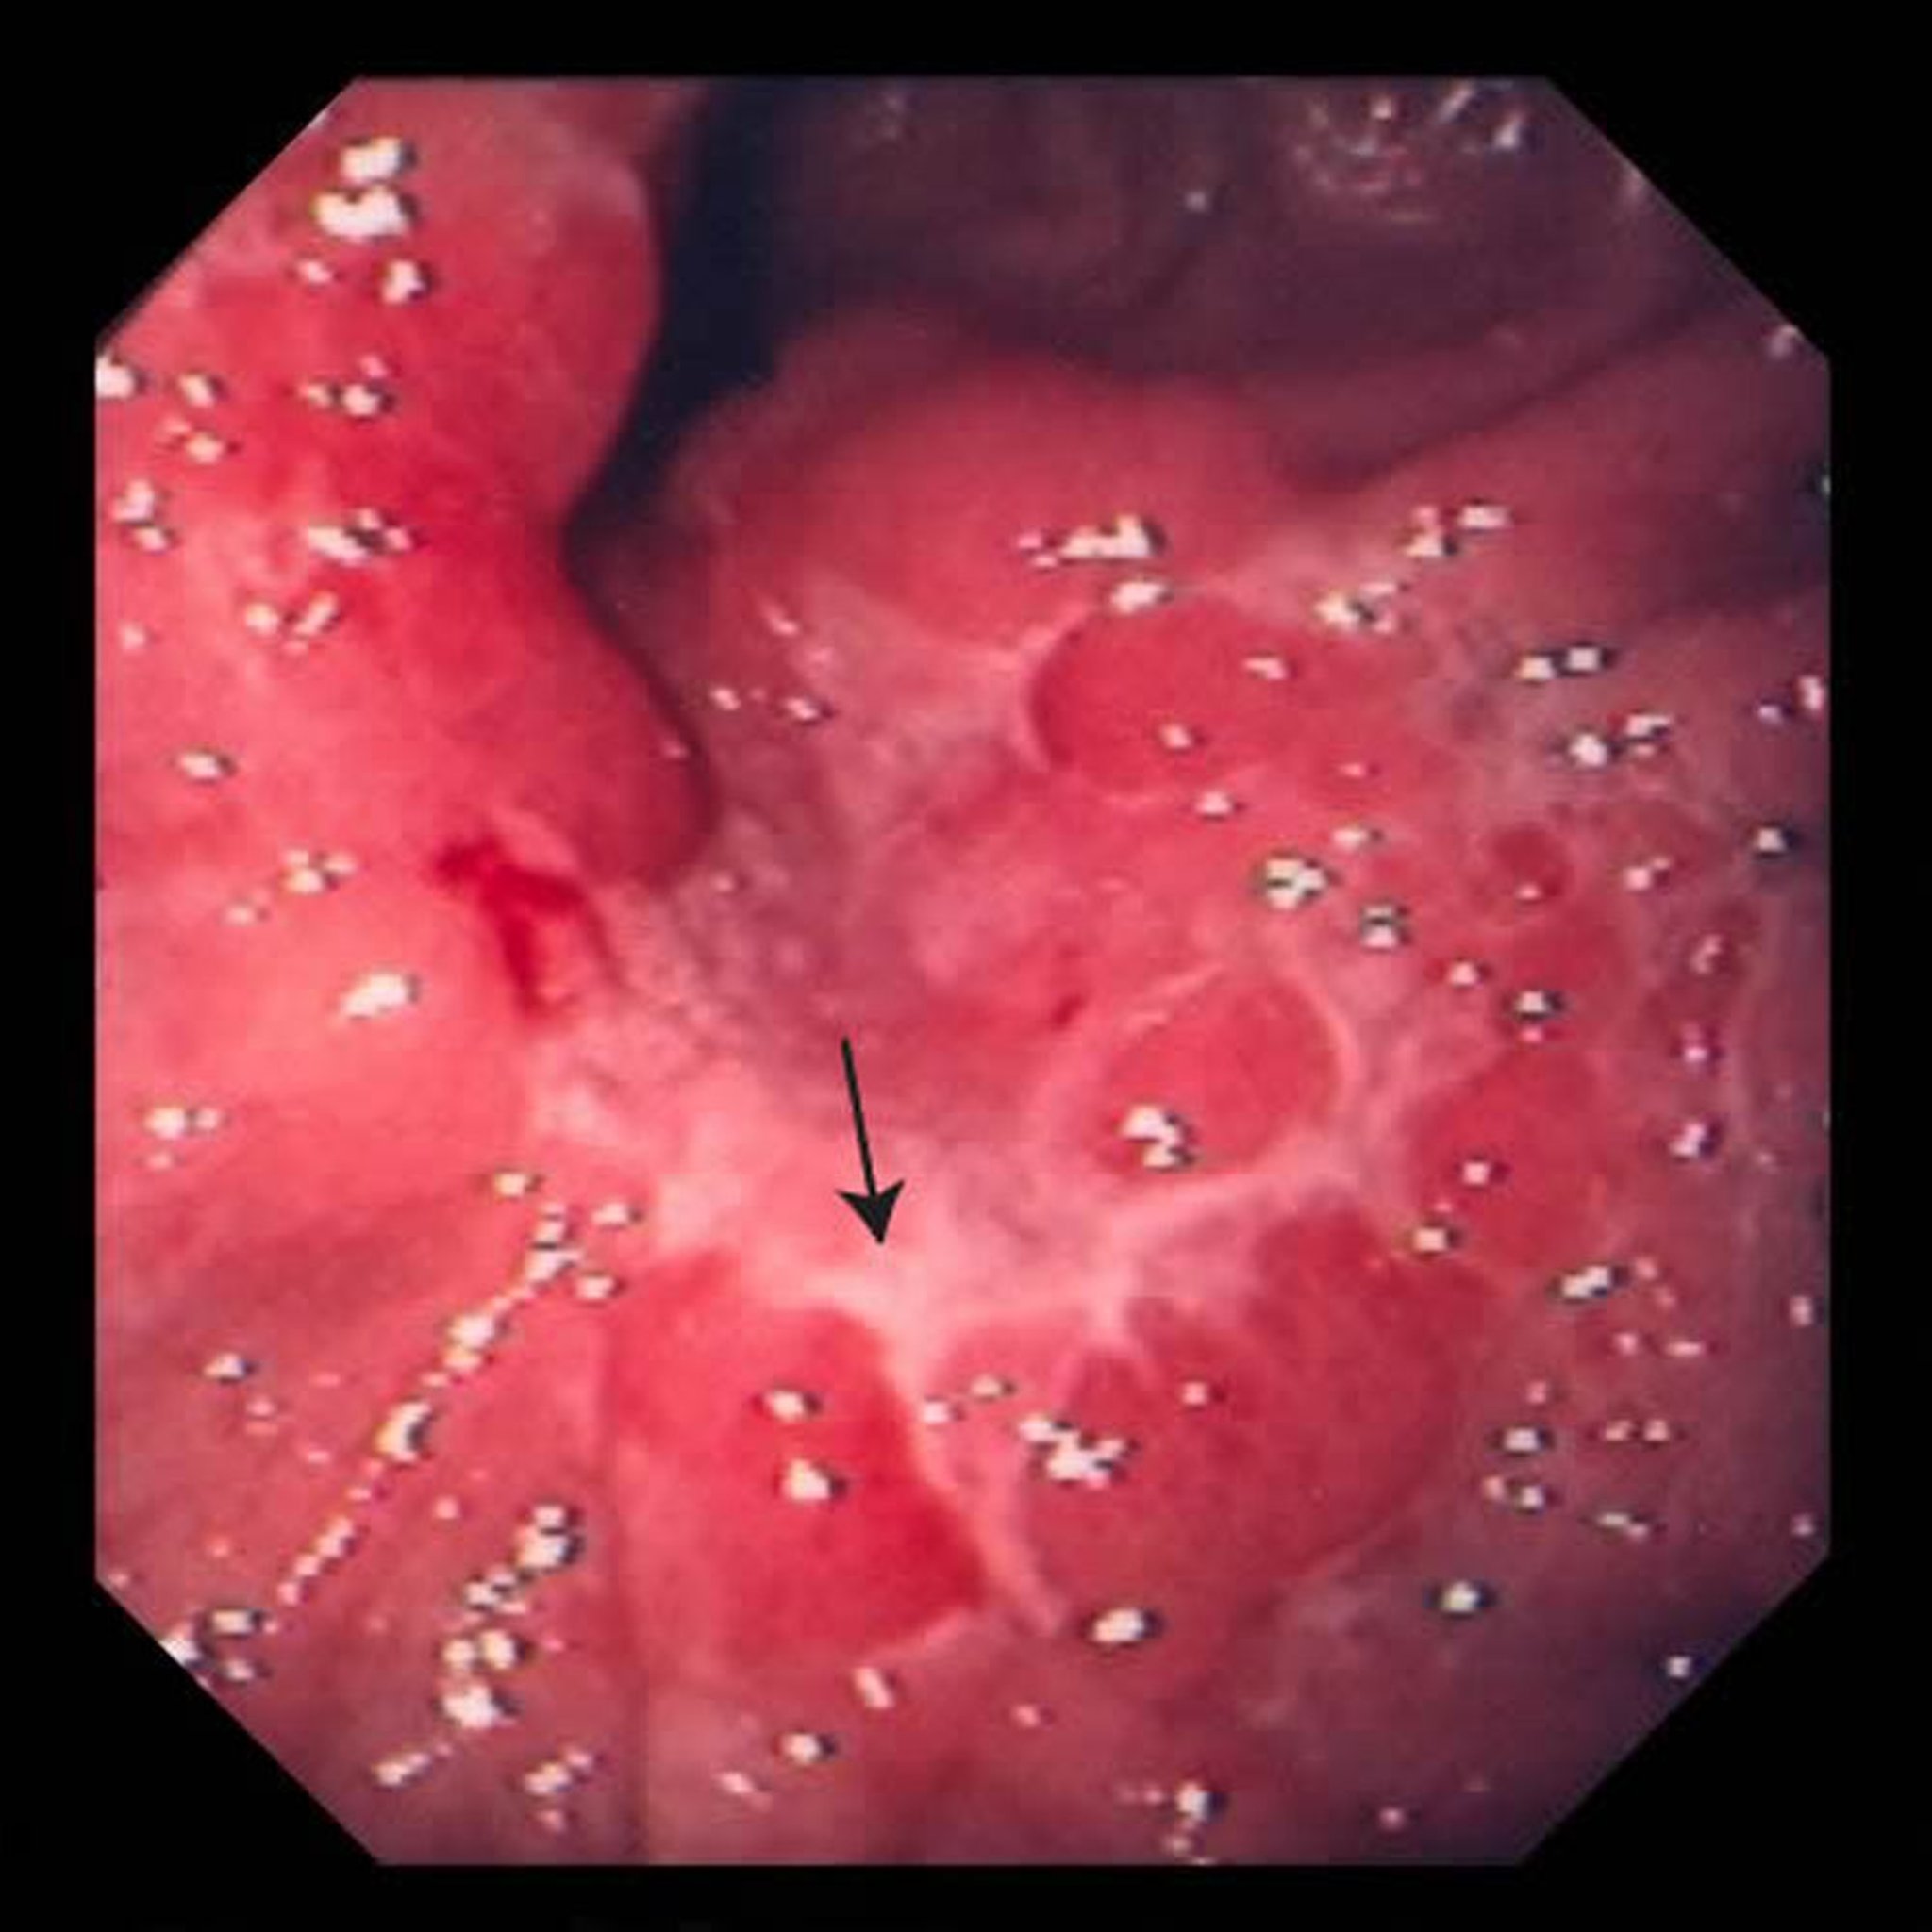

Esta fotografia exibe uma úlcera no estômago (seta). Após uma biópsia, os médicos determinam que era um adenocarcinoma.

Imagem fornecida pelo Dr. David M. Martin.